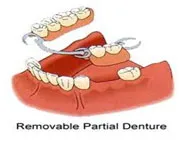

REMOVABLE OPTIONS

Dentures

False teeth on a “plate” that is held by clipping onto your natural teeth. You can remove it from your mouth

3 TYPES

Acrylic

- Most inexpensive option

- May break when dropped

- More bulky

Chrome

- Comfortable

- Less bulk (thinner sections)

- Strong

- Chrome coloured (silver) clips

Flexible

- Comfortable

- Most comfortable, very thin

- Clips are same colour as gums

- Not everyone is a candidate

NOTE: if you have no teeth in either the upper, lower or both jaws, the acrylic and chrome dentures can be made. The only difference being that the denture will not have clips on it that are secured to natural teeth